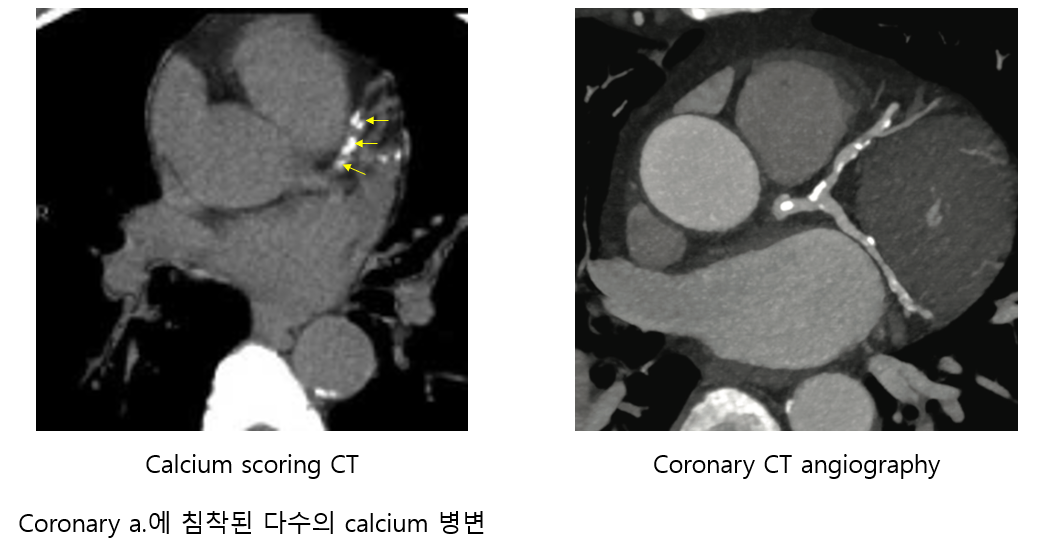

2) Cardiac CT

(1) 관상동맥 칼슘 지수(coronary artery calcium, CAC) 계산

① Noncontrast CT를 이용해 coronary a.에 calcium이 얼마나 많이 침착되었는지 확인

• 0~10: Minimal / 10~100: Mild / 100~400: Moderate / 400~: Severe

② 관상동맥질환 발병 위험을 어느 정도 예측할 수 있으나, calcium이 없는 atherosclerotic plaque도 있음

(2) 관상동맥 CT 혈관조영술(coronary CT angiography, CCTA)

① 조영제를 투여 후 cardiac cycle에 맞춰 엑스선을 조사해 CT를 촬영

② 높은 음성예측도: CCTA상 coronary stenosis가 없으면 관상동맥질환은 거의 배제할 수 있음

③ 단, 심장/혈관의 구조적 문제만 보이며, 기능적 평가는 할 수 없음